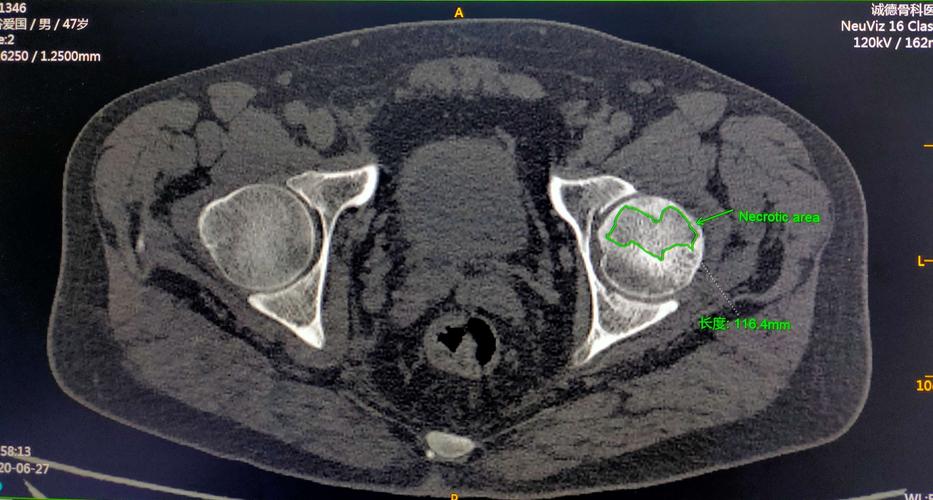

ct显示股骨头坏死区